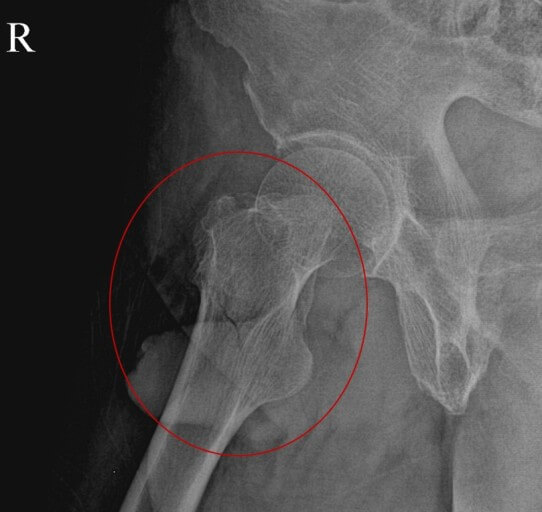

골다공증이란 뼈에서 무기질이 빠져나가 뼈의 밀도가 감소하고 이로 인해 이차적으로 병적 골절을 일으킬 수 있는 대사성 질환으로 주로 흉추(등뼈)와 요추(허리뼈)의 압박골절, 대퇴골 경부와 전자 간 부위 골절, 요골 하단(손목 부위) 골절등을 일으키게 됩니다.

골다공증 진단을 위해, 혈액을 통한 기본 검사인 칼슘과 인, 비타민 D , 갑상선 기능검사, 단백질등의 수치를 검사합니다. 단순 X-ray 촬영과 골밀도(BMD) 검사를 통해 골의 소실 정도를 알 수 있으며 필요시 MRI와 초음파 검사를 하기도 합니다.

골밀도가 -1에서 -2.5이면 골량 감소, -2.5 이하이면 골다공증으로 진단하며, 골밀도가 -2.5 이하면서 신체의 한 부위 이상에 병리적 골절이 있으면 중증 골다공증으로 분류합니다.